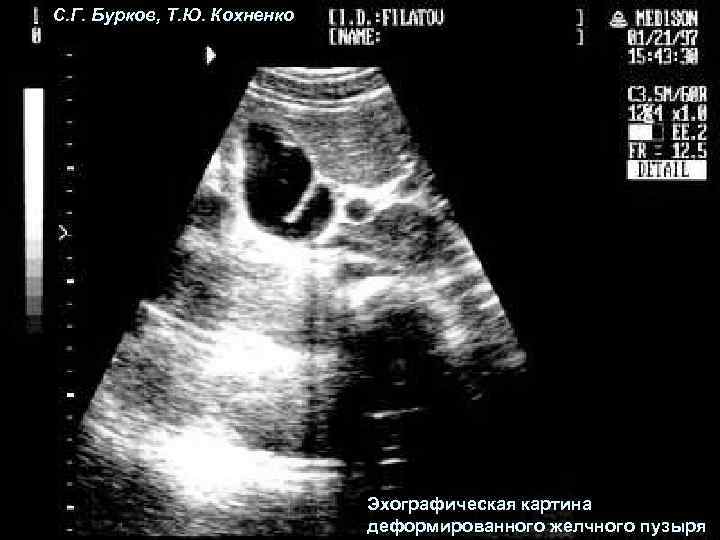

С. Г. Бурков, Т. Ю. Кохненко Эхографическая картина деформированного желчного пузыря